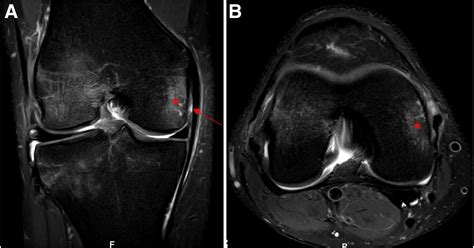

Diagnosing an MCL Tear with an MRI

An Mcl Tear Mri is a non-invasive imaging technique that provides detailed images of the knee joint. MRI uses magnetic fields and radio waves to create cross-sectional images of the body’s internal structures. This allows healthcare professionals to visualize the MCL and other soft tissues in the knee, identifying any tears or damage.

During an *Mcl Tear Mri*, the patient lies on a table that slides into a large, cylindrical machine. The procedure is painless and typically takes about 30-60 minutes. The MRI machine captures multiple images from different angles, providing a comprehensive view of the knee joint.

An *Mcl Tear Mri* can help determine the grade of the MCL tear, which is classified as follows:

An *Mcl Tear Mri* is particularly useful for differentiating between an MCL tear and other knee injuries, such as meniscal tears or anterior cruciate ligament (ACL) injuries. This information is crucial for developing an appropriate treatment plan.